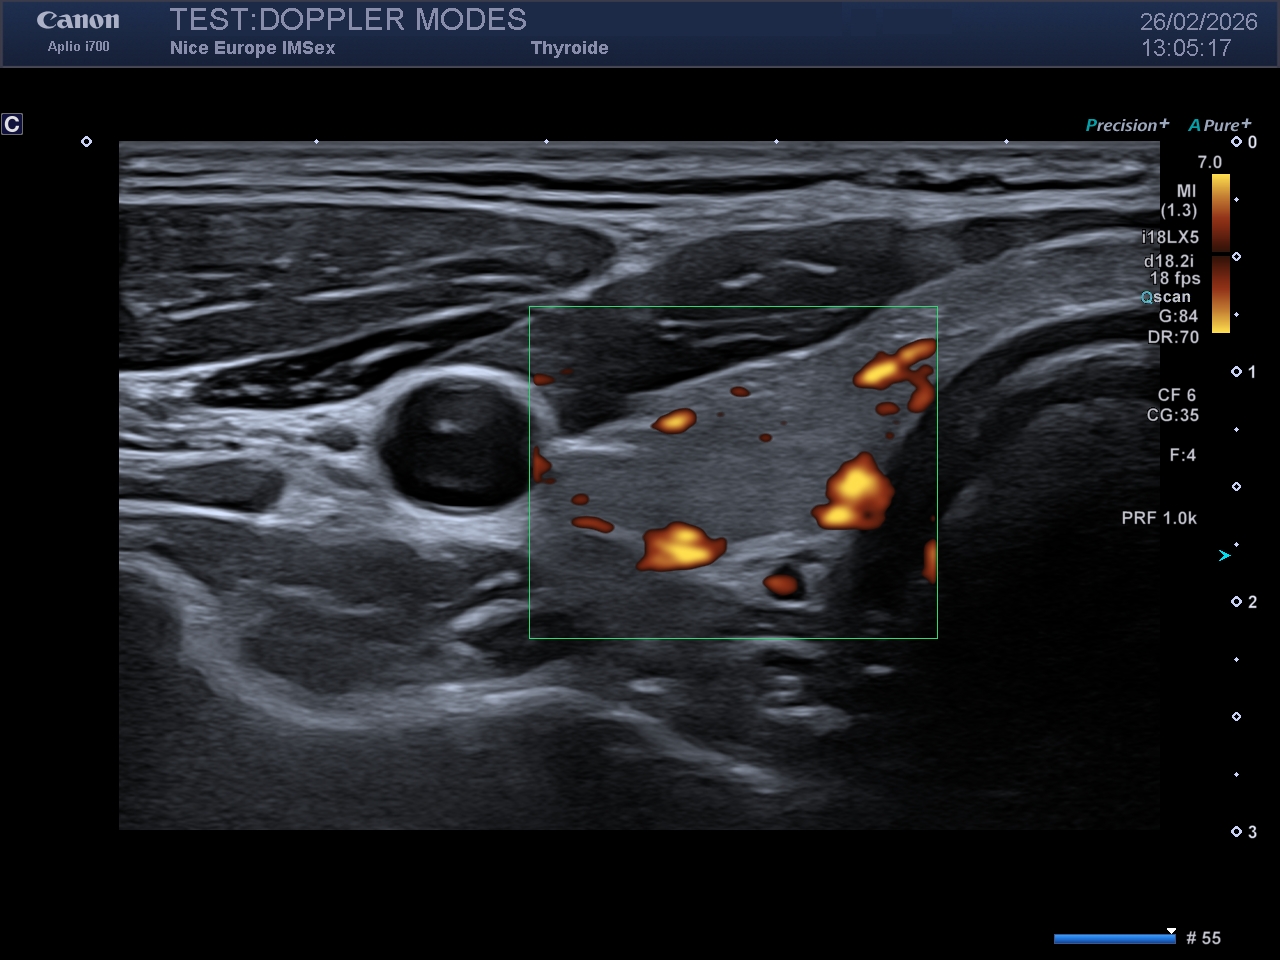

Légende : Image en Doppler Énergie du même rein droit. Notez la plus grande quantité de signal Doppler affichée sur l'image, mais aussi le caractère "grossier" de la cartographie couleur

Les modes microvasculaires de dernière génération (déclinés selon les constructeurs sous diverses appellations telles que SMI - Superb Micro-vascular Imaging, MFI - MicroFlow Imaging, MV-Flow, Micro Angio, LumiFlow, etc.) contournent ce problème grâce à l'imagerie ultrarapide. Au lieu d'émettre des faisceaux focalisés ligne par ligne, la sonde émet des "ondes planes" non focalisées balayant l'ensemble de la zone en une seule émission. Cette technique permet d'acquérir des milliers d'images par seconde.

Le résultat est une cartographie microvasculaire d'une résolution spatiale inouïe, limitant drastiquement les artefacts de débordement (blooming artifact). Ce mode excelle dans la caractérisation fine de l'angiogenèse tumorale ou l'évaluation de l'activité inflammatoire tissulaire.